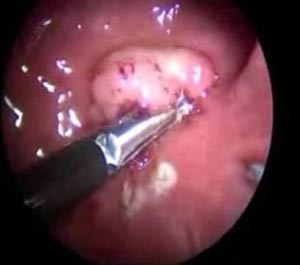

직장은 대장의 마지막 부분으로 길이는 약 15㎝이며 상부, 중부 하부 직장으로 나눌 수 있으며, 천골의 앞면에서 가운데를 따라 내려가 항문에서 끝나요. 직장은 파이프 스타일의 관으로 안쪽에서부터 점막층, 점막하층, 근육층, 장막층 등 4개의 층으로 나뉘어 있죠. 거의 의 직장암은 장의 점막에서 나타나는 선암이며, 뿐만밖에도 유암종, 림프종, 육종, 편평상피암, 다른 암의 전이성 병변 등이 있죠.

선종성 용종은 대장에 생기는 혹으로 대다수 의 대장암은 원인에 문제될 것 없이 선종성 용종이라고 부르는 암의 전 스탭를 거쳐 암으로 발전하게 되겠습니다. 선종성 용종은 증상이 없는 50세 이상의 성인이 대장 내시경을 하게 되었다면 약 30% 정도에서 발견되겠습니다.

선종성 용종이 얼마나 암으로 발달할 위험이 있는지는 용종의 크기와 현미경적 조직 생각에 따라 격차가 있어요. 범위가 1cm보다 작은 경우는 암세포가 들어 있을 확률이 1% 정도이지만 2cm보다 크면 암세포가 들어 있을 확률이 약 35~50%나 되겠습니다. 또한 조직검사에서 융모성 성분을 충분히 내포하고 있을 경우 암으로 추진할 가능성이 높아지고요.